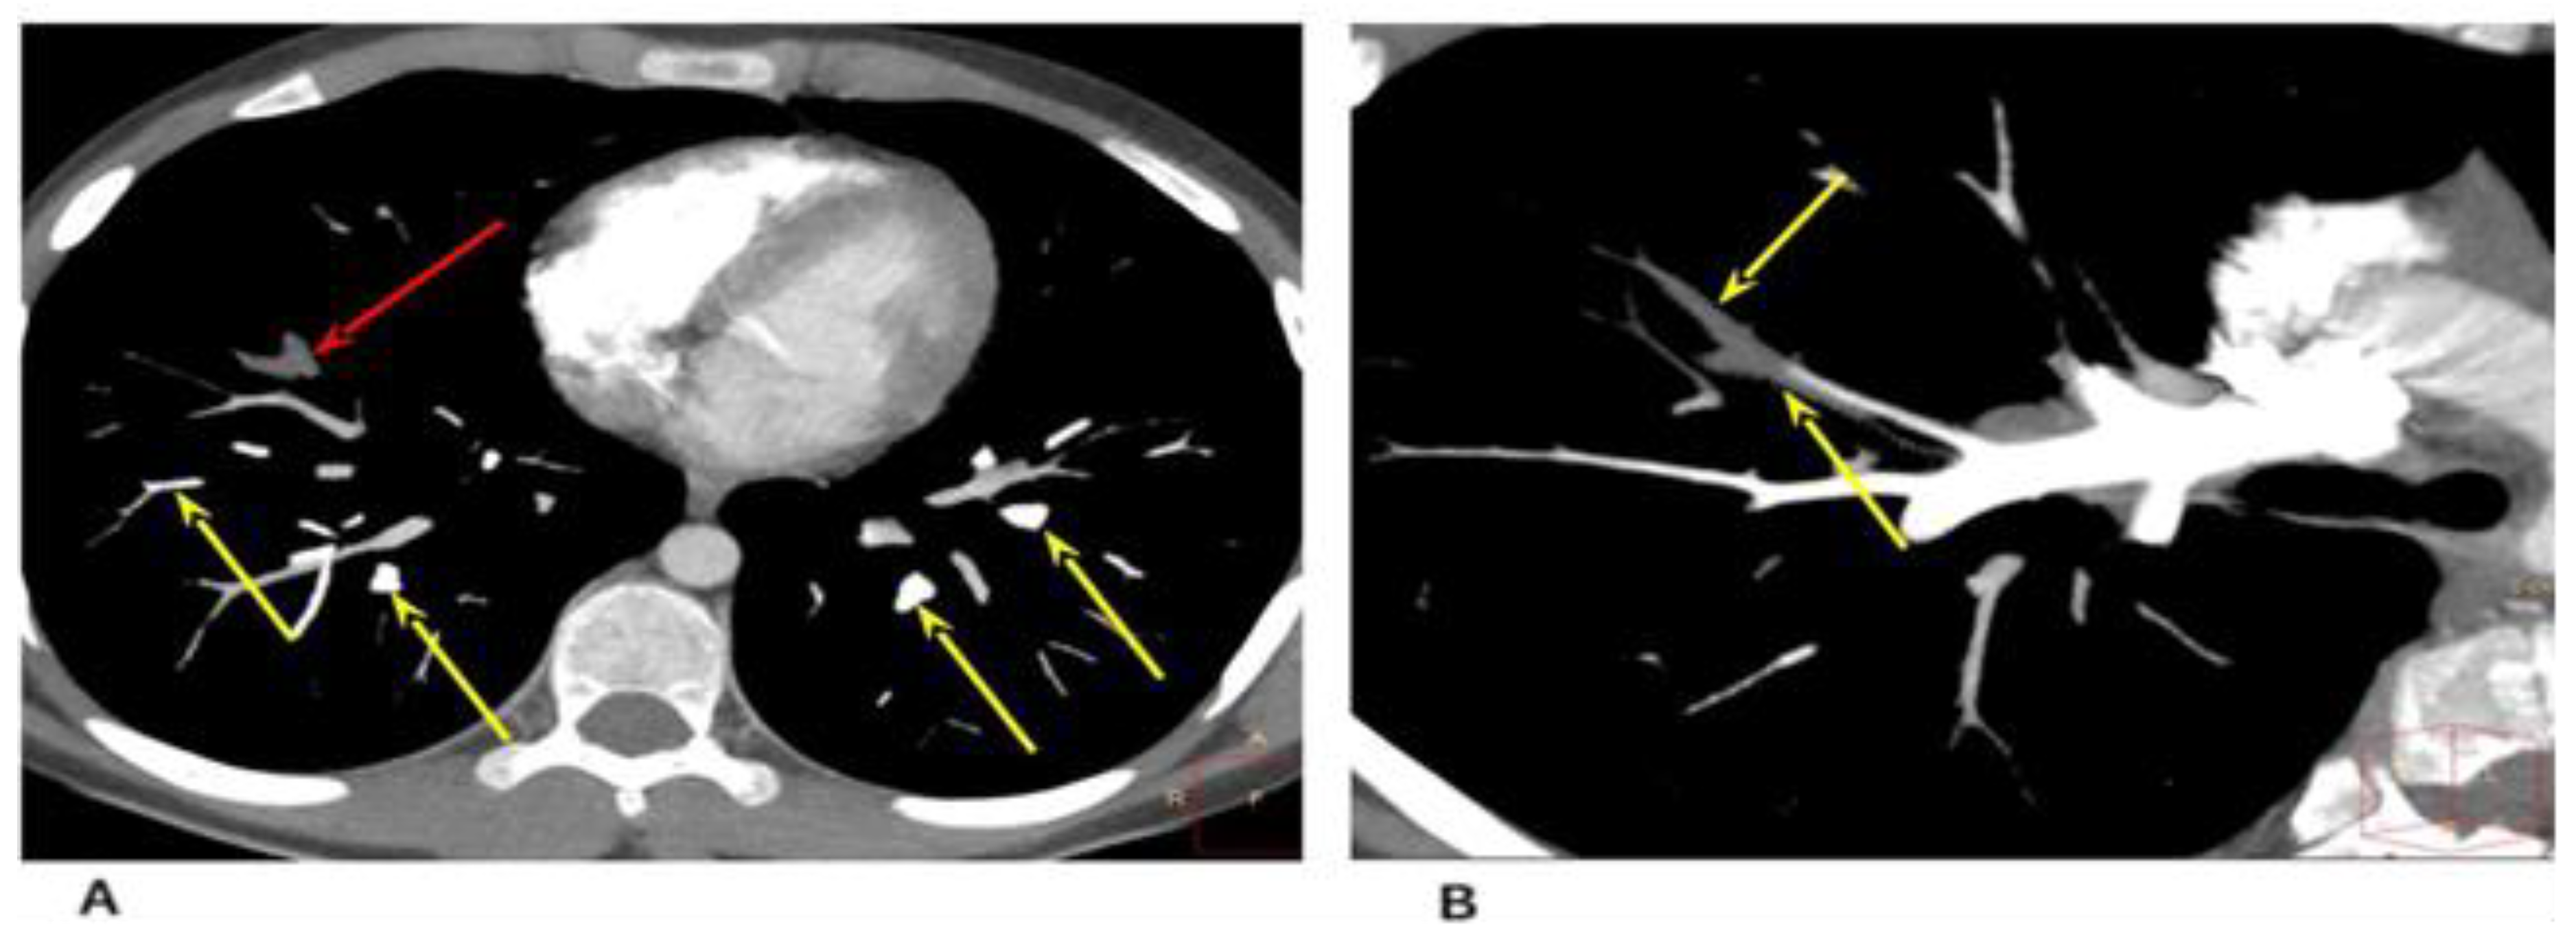

Chest computed tomography (CT) was performed with the use of a contrast agent (Figure 3).

Figure 3.

Cardiac CT angiography, axial plane, maximum intensity projection (MIP), vascular mode. (A) Contrasted distal branches of the pulmonary artery (yellow arrows). Contrasting defects in the distal branches of the A8 right lung (PE—red arrow). (B) Contrasting defects of the distal branches of A8 of the right lung (PE).

The CT and CT angiography examined areas of increased density of the ground glass type (GGO); defects in contrast with the distal branches of A8 of the right lung (PE) were diagnosed. In the anteromedial sections of the right atrium, at the level of the tricuspid valve, an extended avascular hypodense area of an irregular shape was determined (up to 16.5 × 7.5 × 9 mm in size).

For differential diagnosis and exclusion of heart formation, positron emission tomography was performed—chest CT: fluorodeoxyglucose—positive neoplasms in the projection of heart structures (including the right atrium) were not detected.

The data of the chest computed tomography (CT), including contrast agent for determination of vascular thrombosis, are shown in Figure 4.

Figure 4.

Heart CT angiography, axial plane, and pulmonary regimen in a 7-year-old child. (A) Reduction in lung pneumatization due to extensive confluent ground glass attenuation. (B) Free fluid was determined in the pleural cavities on both sides.

The CT and CT-angiography, a diffuse decrease of the lung pneumatization was diagnosed due to extensive confluent “ground-glass” attenuation, and free fluid up to 25 and 30 mm was determined in the pleural cavities on the right and left, respectively. The signs of left-sided thromboembolism of subsegmental branches of the A8 pulmonary artery and heterogeneity of pneumatization were diagnosed (Figure 4).

Heart CT, axial and coronal angiography, and pulmonary mode after 4 weeks.